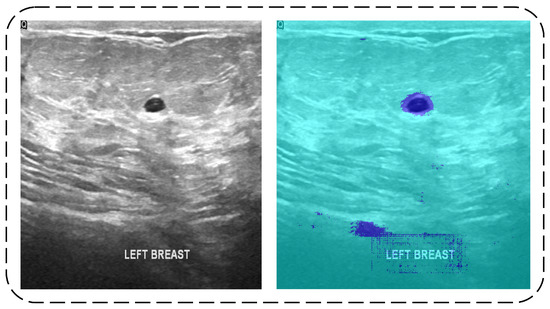

3.1. Segmentation

3.1.1. Dilated Semantic Convolutional Neural Network

3.1.2. Erosion